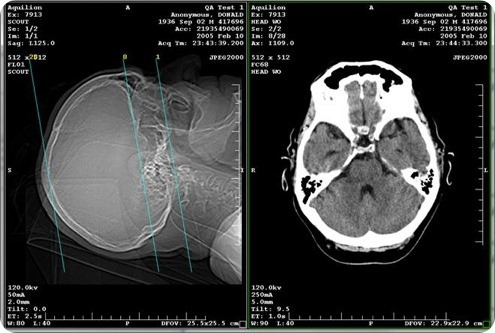

The most common method of image sharing over the past decade has been compact discs (CDs). Physicians place exams and reports on CDs and give them to patients to take to their medical appointments for treatment or second opinions; however approximately 20 percent of these CDs contain corrupt or bad files.

When a CD is unreadable or lost, a patient is usually re-scanned, which exposes the individual to added radiation and delays treatment. In fact, there are more than 600 million exams done each year in the U.S. and 10 to 20 percent of those are duplicate exams - totaling $10 billion in excess.

Collaborative platforms are decreasing healthcare costs and empowering care coordination by allowing hospitals, doctors and patients to access and share medical images in real-time from Internet-connected devices.

Medical image sharing helps streamline transfer and referral processes, eliminate duplicate testing and improve patient outcomes and care coordination.